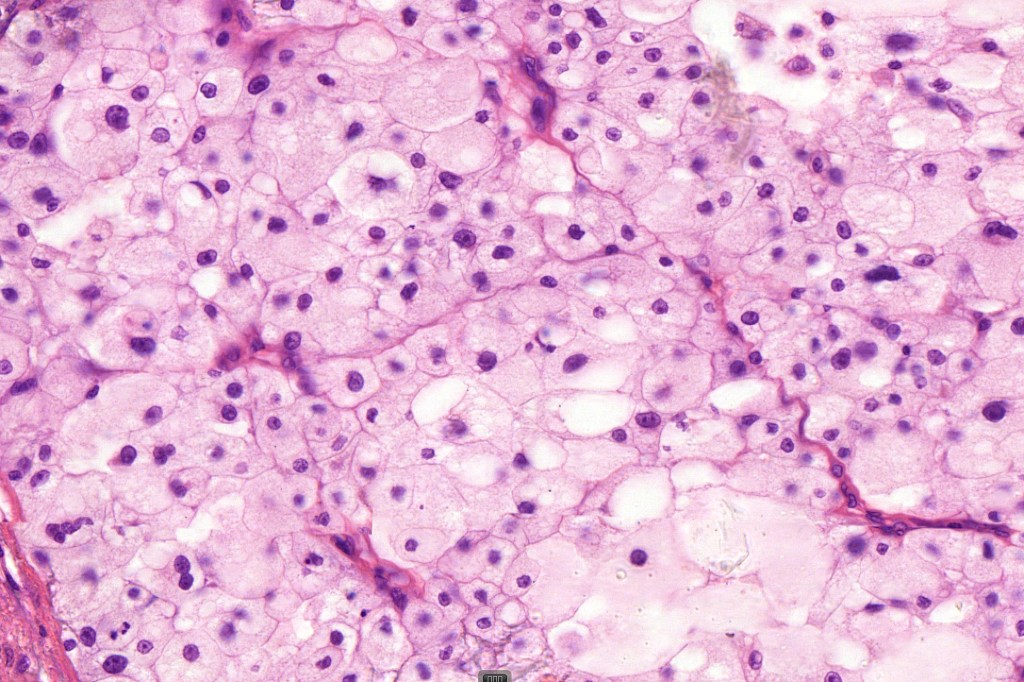

•Enlarged cells with copious eosinophilic, foamy or clear cytoplasm (some authors include melanoma with clear cell change in the same category)

•Variable pigmentation

•Nuclei vesicular or hyperchromatic

•Pleomorphism is not generally marked and indeed can be very subtle

•Variable mitotic activity

•DPAS granules

•Thought to be a result of abnormal or degenerative melanosome change